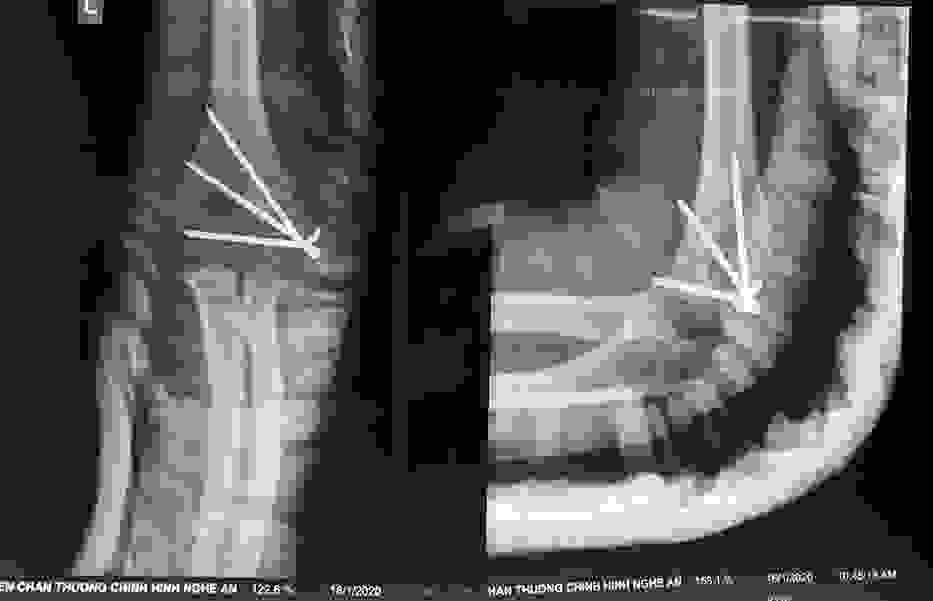

Phẫu thuật thành công ca bệnh hiếm gặp...khớp giả bẩm sinh xương chày

26/06/2019 17:00

Đã xem: 3183

Bệnh viện Chấn thương- Chỉnh hình Nghệ An, vừa phẫu thuật thành công cho bệnh nhi khớp giả bẩm sinh xương chày